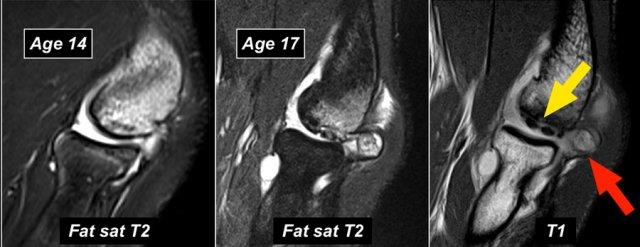

Những hình ảnh này của một cầu thủ bóng chày trẻ, xuất hiện với triệu chứng đau khuỷu tay lúc 14 tuổi.

Hình ảnh T2W-fatsat cho thấy phù tủy xương và có thể có gãy xương dưới sụn.

Rõ ràng là có người đã bảo cậu bé tiếp tục ném bóng, vì cậu quay lại ba năm sau khi 17 tuổi và bạn có thể thấy điều gì xảy ra khi người ta thúc ép quá mức để biến những đứa trẻ này thành vận động viên chuyên nghiệp.

Hình ảnh T1W cho thấy sự phân mảnh (mũi tên vàng) với một mảnh xương tự do (mũi tên đỏ).

Hình ảnh T2W chứng minh rằng mảnh xương không ổn định do có tín hiệu cao giữa mảnh xương và xương cánh tay.

Khi nội soi khớp, có thể thấy sự lõm xuống và không đều của sụn chỏm con.

First the loose bodies were taken out.

Sau đó, thủ thuật OATS thường được thực hiện, mà chúng ta sẽ thảo luận ngay bây giờ.